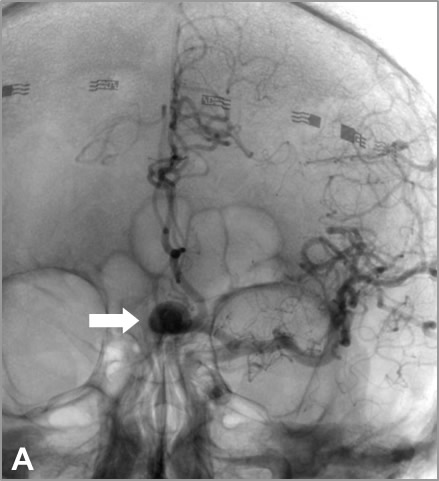

En 2017 sufrió traumatismo craneal leve en accidente de tráfico, motivando la realización de neuroimagen en la que se identificó un aneurisma de arteria comunicante anterior. Posteriormente se realizó arteriografía diagnóstica, confirmando la presencia de un aneurisma sacular polilobulado de arteria comunicante anterior, con diámetros aproximados de 13mm x 9 mm y cuello de 4 mm. Como variante de la normalidad, el paciente presenta además una duplicación del segmento A2 abarcando el trayecto pericalloso, evidente en las series angiográficas de arteria carótida interna izquierda, cuyo origen se encuentra en íntima relación con el cuello aneurismático, y que podría corresponder a una persistencia de la arteria mediana del cuerpo calloso (variante con una prevalencia de entre 3 y 6%1,2).

A, B: Series angiográficas en proyecciones AP y L de arteria carótida interna izquierda, observándose aneurisma de arteria comunicante anterior (flechas negras). C: Reconstrucción 3D. Nótese origen adyacente al cuello aneurismático y trayecto de arteria cerebral anterior accesoria (flechas blancas).